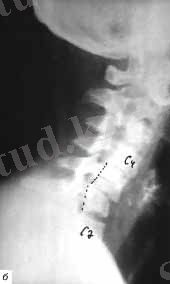

- С2 омыртқасының доғасының сынығы -хэнгман сынығы («асылған » сынық - рис. 2, б) ;

Рис. 2. Омыртқаның мойын бөлімінің Рентгеногграммасы

а- схема, б - хэнгман сынығы ( «асылған »), в - С2 омыртқа тісінің сынығы

А типі - омыртқа денесінің компрессиялы сынығы, Втипі - алдыңғы артқы комплекстердің зақымдануы, С типі -ротациялы алдыңғы артқы комплекстердің зақымдануы . Омыртқаның мойын бөлімінің анатомиялық құрылымының ерекшелігіне байланысты өзіндік жіктелуі бар, ал төменгі сегмент зақымдануы тұрақсыз және с типті. рис. 4) .

Радиологиялық зерттеулер. Тексеруді көрсеткіш екі проекциялы ретгенннен бастайды, алдыңғы артқы және бүйір, рентгенограмманың ортасында клинасмен анықталған зақымданған ошақ орналасады. Алдынғы артқы проекцияда көлденең өсінділер зақымдануы, омыртқалардың бүйірлык шығулары, ал қалған сынықтар бүйір проекцияда жақсы көрінеді. Әдеттегі сынықтардардың орнын білу кезінде рентгенологиялық тексеру барысында барлық кеуде бел ауысуын (бел омыртқаларының сынығына күдіктенгенде ) және мойын- кеуде ауысуында төменгі мойын омыртқаларының сынығын анықтағанда, науқас қолы төменге қарай, иық және иықүсті буының төмен түсіру арқылы рентген суретін жасаймыз. Рентгенограмманы бағалаған соң, керек жағдайда томограммыа, қиғаш проекциялы рентгенограмма, жасауға болады, Омыртқаның шығуы болатын болса, жоғары орналасқан омыртқа шыққан деп есептеледі. (рис. 5 а, б)

Омыртқа денесінің сынығының рентгендік көрінісі ретінде бүйір проекциядағы сына тәрізді деформация болып табылады. (рис. 5, в) .